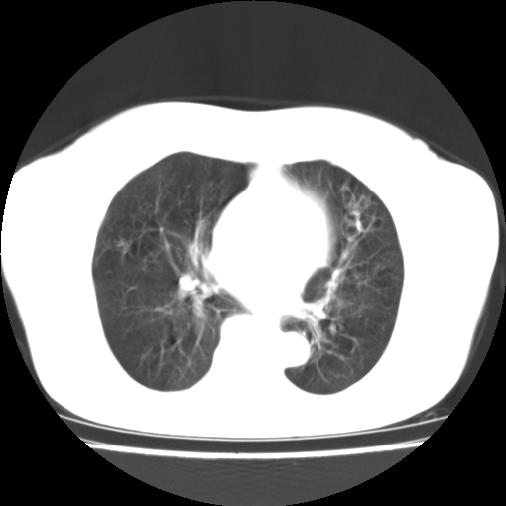

标题: CT16957:F56Y,这是先天性肺囊肿,还是支气管扩张??? [打印本页]

标题: CT16957:F56Y,这是先天性肺囊肿,还是支气管扩张???

女性病人,56岁,反复咳喘30余年,伴大量脓痰,偶有痰中带血。

此病例在科室里有较大的争议,我认为是先天性肺囊肿(理由是:两者起病年龄都较轻,都有咯血及脓痰的症状,而先天性肺囊肿壁薄;而支扩的囊腔旁一般都能看到伴行的血管影,形成“印戒”征)。以上为个人的意见,请高手们指点一下。

本例应为支气管扩张并感染,与囊肿区别在于其大小,分布,壁改变,与肺动脉关系,形态等来鉴别,要点大家都说得差不多了,囊肿要大些,分散些,靠外围一些,而支扩靠内一些,聚拢些,小一些且易聚拢呈葡萄状,不能单从囊壁厚度来评价,特别是有粘液栓类的改变更加支持支扩,有时支扩亦与囊肿混在一起并存.个人意见仅供参考.